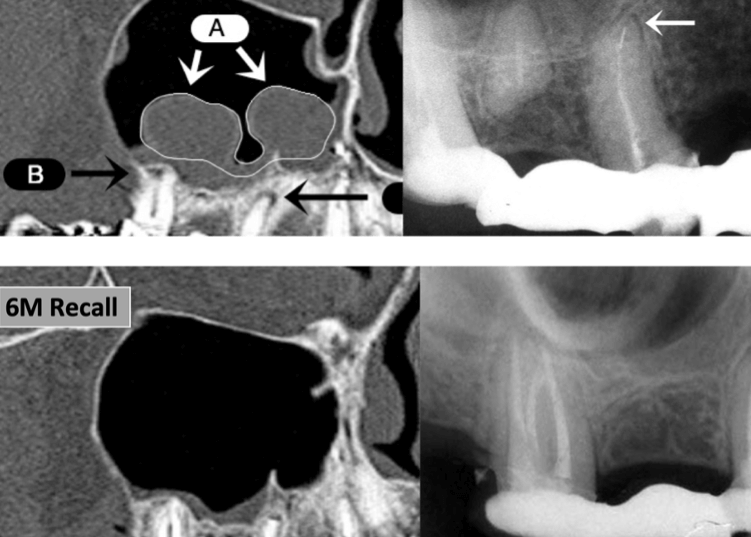

No statistical significance was found between endodontic therapy and abnormalities in maxillary sinus (p=0.4). No statistical significance was found in mucosal thickness between different populations (p=0.2). A statistically significant correlation was found between the distance from apex to sinus floor and thickness of sinus mucosa (p=0.001) (Fig 2).

5. Predictable and efficient root canal disinfection and treatment can heal sinus abnormalities (Fig 3).